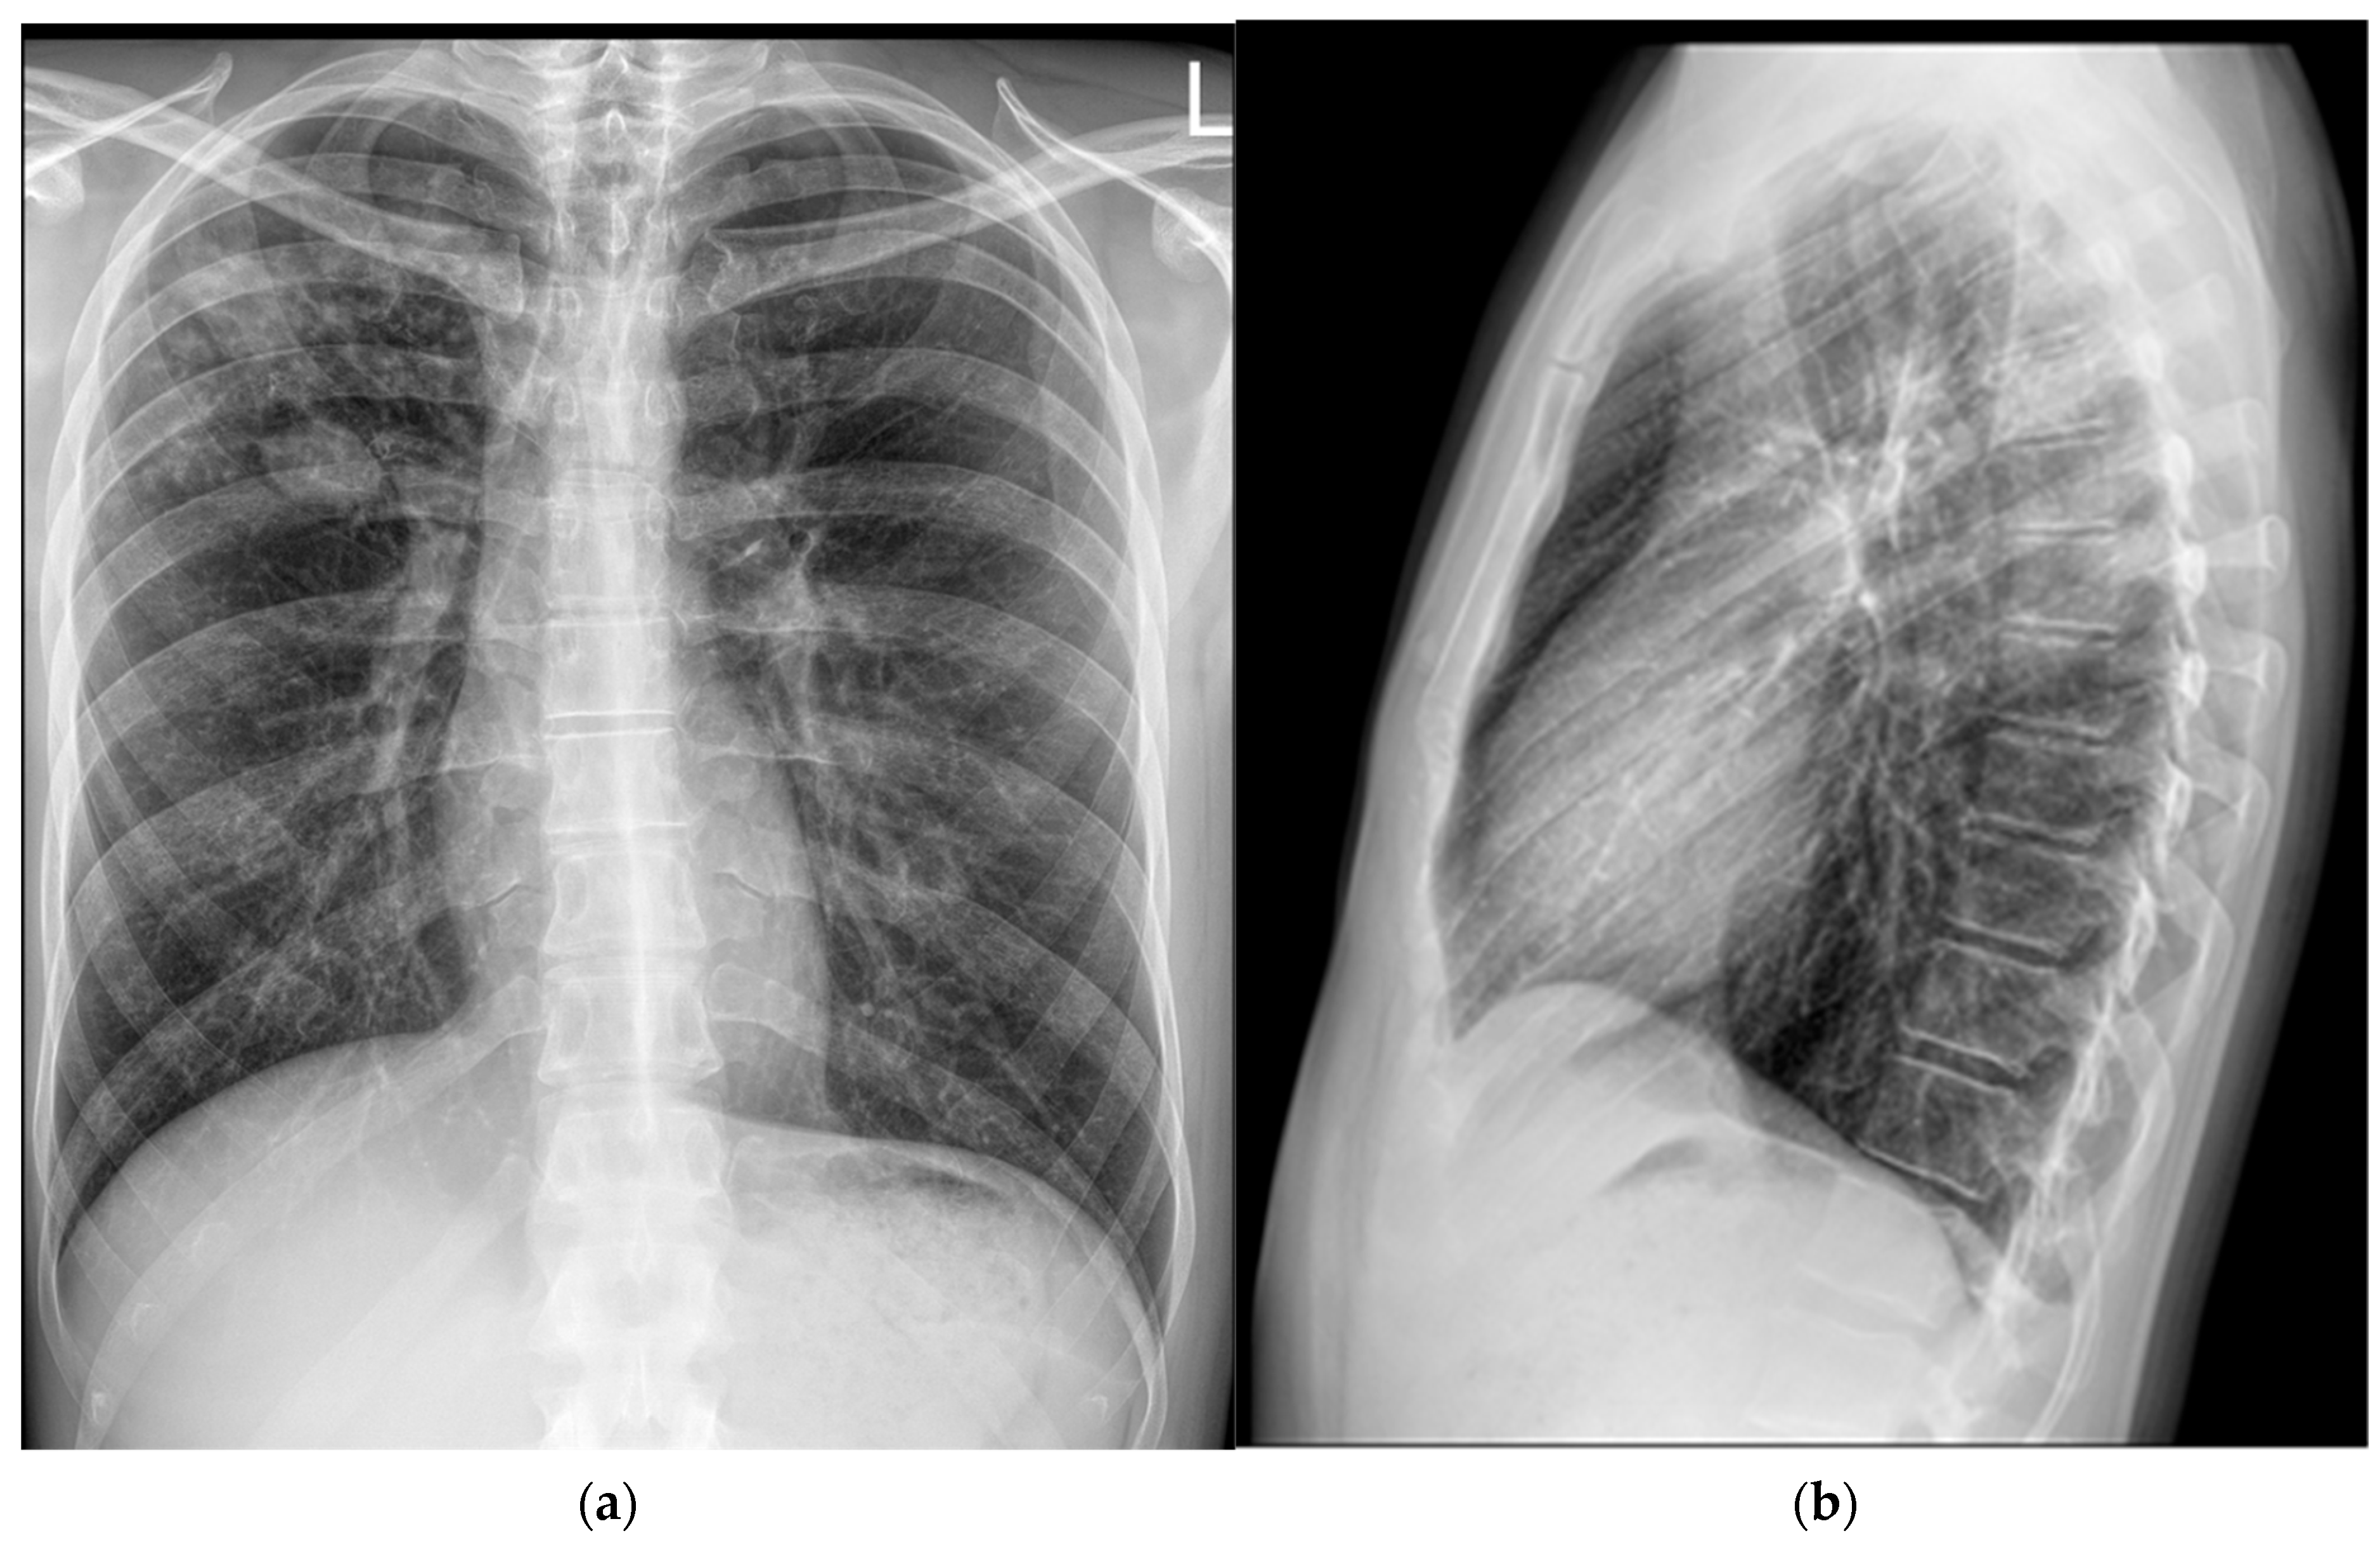

Intrathoracic lymphadenopathy was present. On 30 April 2024, the patient was transferred to the Department for Lung Diseases and Drug-Resistant Tuberculosis at Klenovnik, Varaždin General Hospital, where a shortened six-month treatment regimen (bedaquiline, pretomanid, linezolid, and moxifloxacin: BPaLM) was promptly initiated [12]. This was the first patient in Croatia diagnosed with a monoresistant form of TB resistant to rifampicin who met the criteria for the aforementioned treatment regimen. As pretomanid was not registered in Croatia at the time, it was not possible to commence the full treatment regimen immediately, in accordance with the recommended treatment algorithm. The estimated time for obtaining the drug was up to three weeks. Consequently, therapy was initially started according to the BLM protocol, including bedaquiline 100 mg (four tablets daily), which the patient received until 21 May 2024, and thereafter bedaquiline was continued at a dose of 200 mg three times per week (Mondays, Wednesdays, and Fridays). Linezolid was administered at an initial dose of 1200 mg daily for 2 weeks, followed by 600 mg daily for the next 12 weeks, and then reduced to 300 mg daily for the final 8 weeks. Moxifloxacin was given at a dose of 800 mg daily during this interim period. Pretomanid treatment was initiated on 12 June 2024, at a dose of 200 mg once daily. At that time, the moxifloxacin dose was reduced to 400 mg daily, and the patient continued therapy as per the BPaLM regimen. Throughout the entire course of therapy, regular ECG monitoring was performed, with no significant QTc interval prolongation observed. Leukocyte counts remained within normal limits, with no episodes of leukopenia. The patient did not report any locomotor symptoms, and no clinical signs of polyneuropathy were detected. Control sputum samples taken during May were AFB smear-negative, while cultures from collected sputum samples became negative in June. Subsequent sputum samples—collected monthly, two per sampling (total of nine additional samples) by the end of hospitalization—remained negative for both direct smear microscopy and culture. Chest X-rays showed complete resolution of the previously described cavity in the right upper lobe, with a persistence of soft tissue infiltrate with oval-shaped opacity in the same region (Figure 3).

Figure 3. Follow-up chest X-rays (5 June 2024) show complete resolution of the previously described cavity in the right upper lobe. However, a stable soft tissue infiltrate with oval-shaped opacity persists in the same region: (a) frontal presentation; (b) lateral presentation.